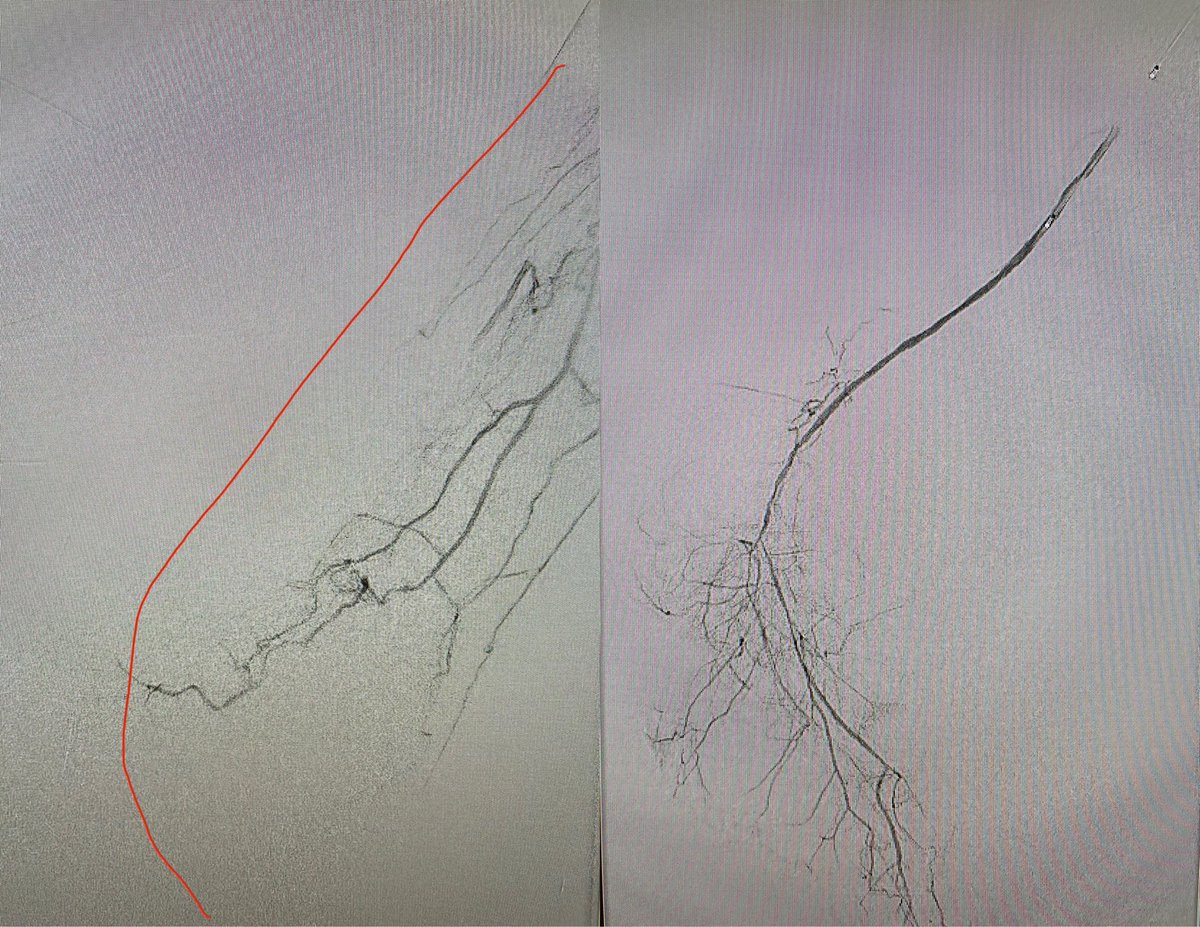

The modified Schmidt technique is a powerful tool to recanalize distally occluded tibial and inframalleolar vessels. Success rates are improved with use of EVUS for image guidance. #clifighters #stopthechop #savealeg

JohnAFryMD's tweet image. The modified Schmidt technique is a powerful tool to recanalize distally occluded tibial and inframalleolar vessels. Success rates are improved with use of EVUS for image guidance. #clifighters #stopthechop #savealeg